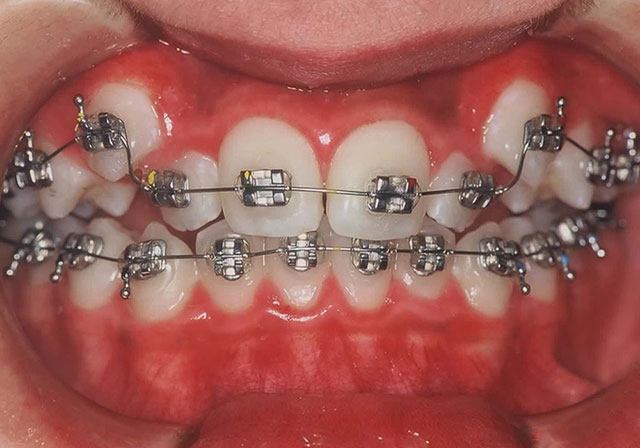

Step5

各歯にブラケットを取り付け正しい位置に歯を並べます。